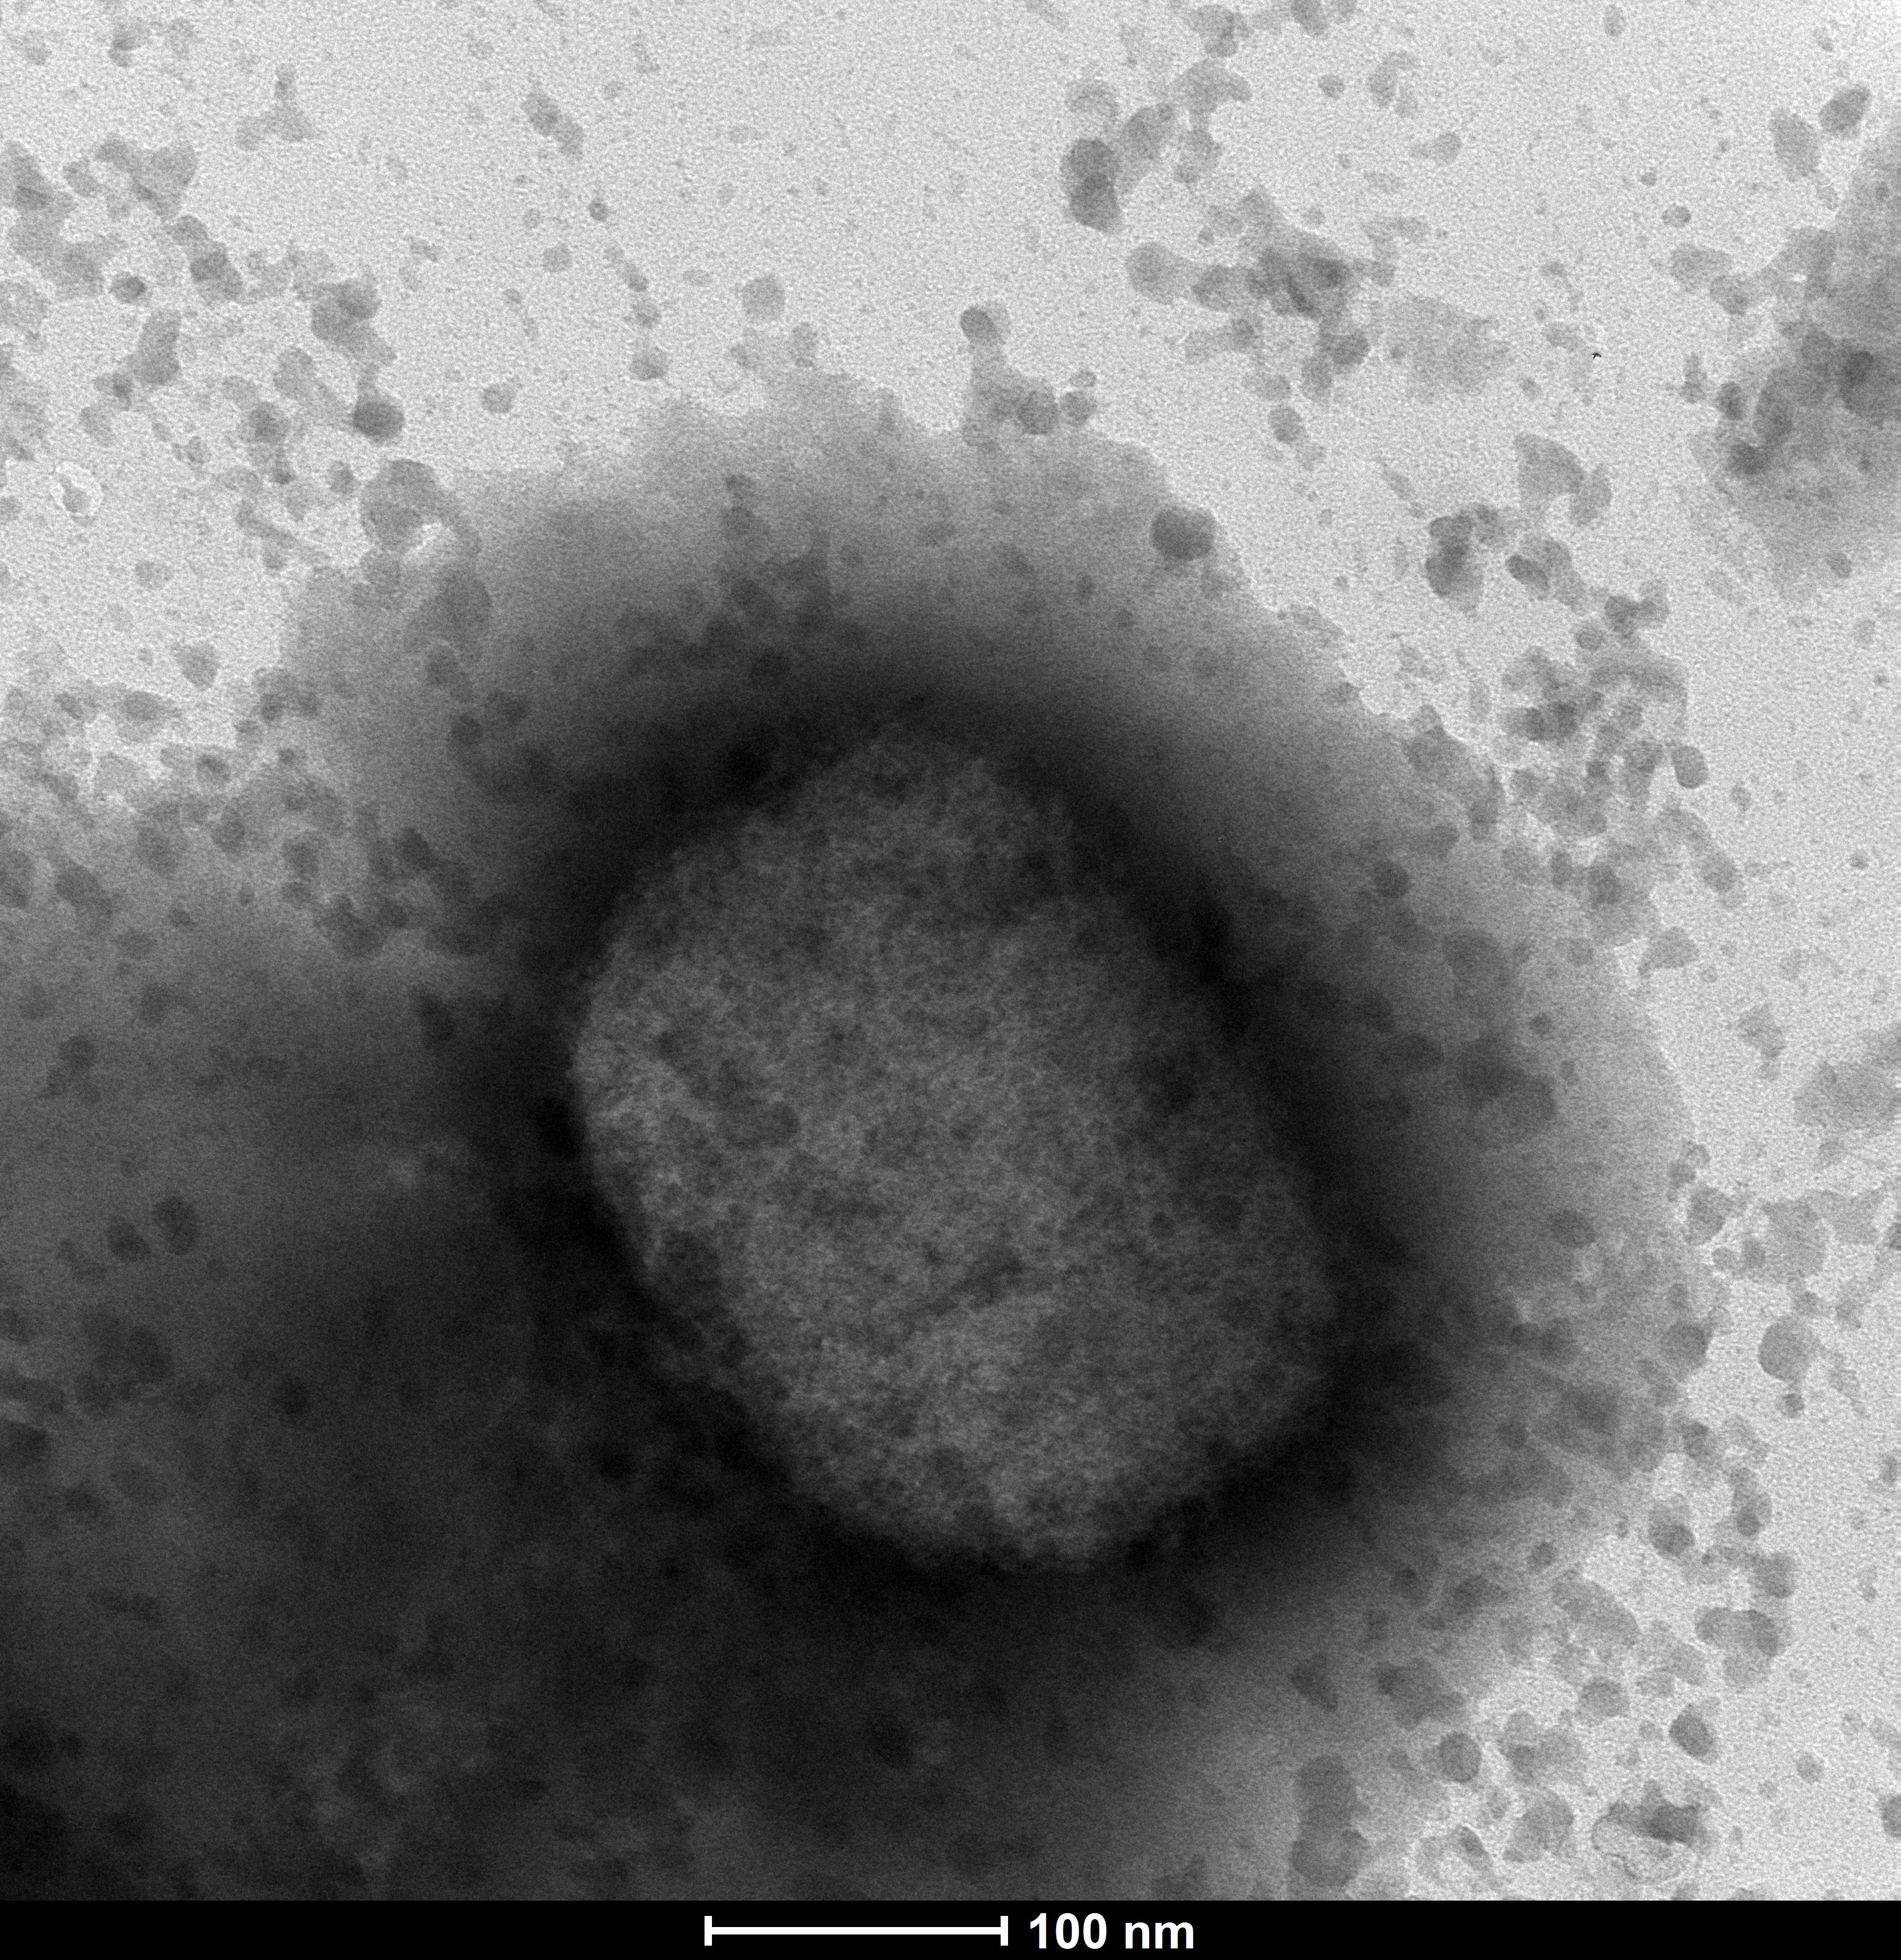

INFORME CIENTÍFICO-DIVULGATIVO: UN AÑO DE CORONAVIRUS SARS-COV-2 * Este informe resume el conocimiento adquirido a lo largo de 2020 en torno al coronavirus SARS- CoV-2 y está realizado con la...